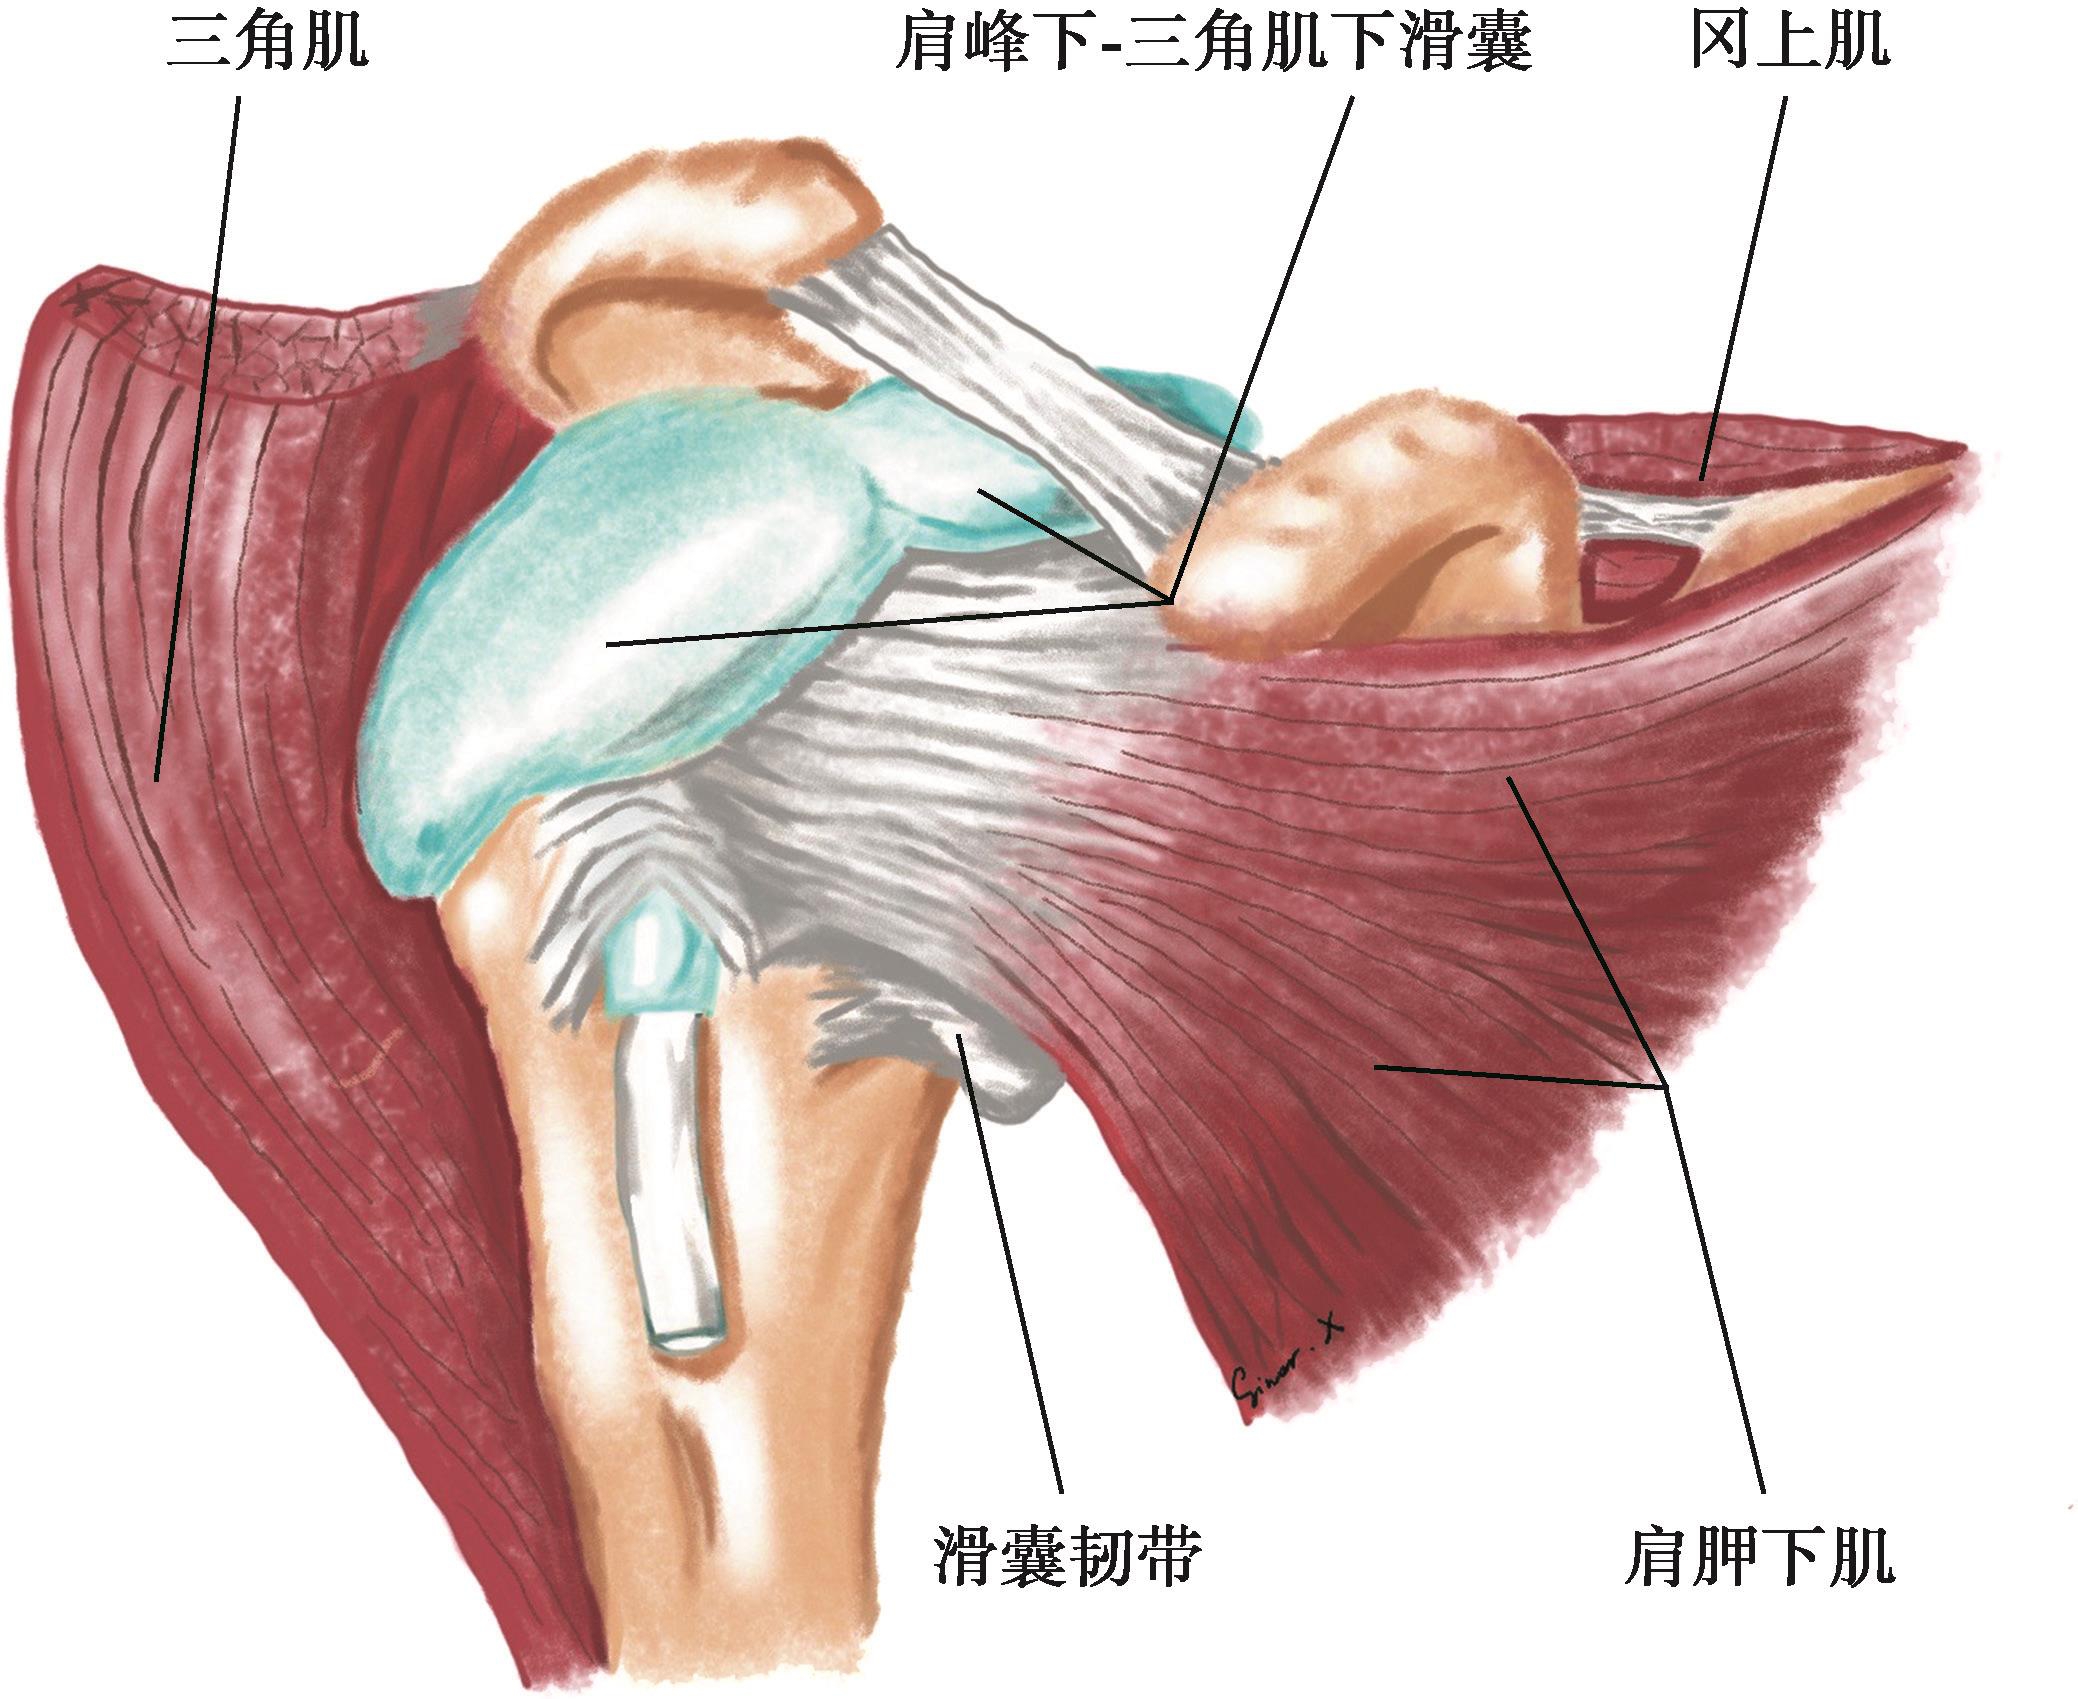

肩峰下-三角肌下滑囊(subacromial-subdeltoid bursa,SASDB),又称肩峰下滑囊或三角肌下滑囊,是全身最大的滑囊之一,位于肩峰、喙肩韧带和三角肌深面筋膜的下方,肩袖和肱骨大结节的上方(图2-1-1)。因肩关节急性炎症或慢性劳损,滑囊容易发生炎症,表现为滑囊增厚、滑膜炎或积液,引起肩部疼痛和活动受限。正常情况下,该滑囊是一个封闭的囊袋样结构,不与肩关节腔相通,当肩袖发生滑囊面或全层撕裂时,滑囊往往与关节腔相通。

▲ 图2-1-1 肩峰下-三角肌下滑囊解剖示意图